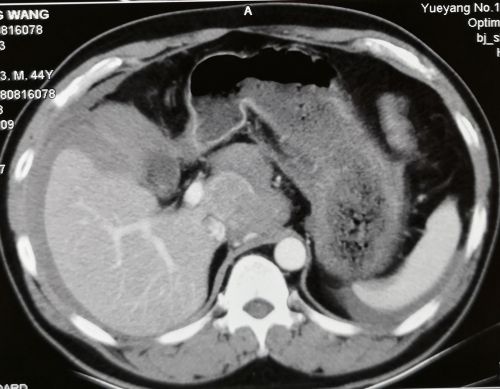

1段和5段的肿瘤。

接到通知后,我立即驾车赶赴岳阳,到达病人身边时已是晚上7点。在仔细查看病人的临床资料并做了体格检查后,我发现病人病情危重:患者男性,44岁,病史较为典型,由慢性乙肝发展为肝硬化,再转化为原发性肝癌,突发肝癌破裂大出血,虽经介入止血治疗,但病人腹腔内有大量积血,估计超过2000ml,血红蛋白仍较低,不排除仍有出血。肝内肿瘤位于1段和5段,1段肿瘤已破裂,周围形成血肿,且位置深,处理有难度。

与陈鹏主任的团队讨论后,我们认为急诊手术是抢救病人生命的最重要的治疗措施,手术的目的:1 止血,这是救命的关键;2 如条件允许,尽量切除肝内肿瘤,清除腹腔内积血;3 配合使用腹腔热灌注化疗,杀灭腹腔内可能残留的肿瘤细胞,减少术后播散和种植转移。按照“救命第一”的原则,制定以上“三步走”的治疗方案。我们和病人家属沟通后,家属非常理解,立即签字同意手术治疗。

晚上8点手术开始,探查发现腹腔内积血和血凝块2500ml,清除后发现肝脏情况和术前分析相符。打开小网膜囊,套通肝十二指肠韧带,切除胆囊,显露1段和5段的肿瘤。阻断第一肝门,先完整切除1段肿瘤,再剥除5段肿瘤,彻底止血。这两步顺利完成后,留置4根引流管,用5-Fu+奥沙利铂方案43℃行腹腔热灌注化疗60分钟。手术过程顺利,达到了术前设定的较为理想的目标,输血浓缩RBC6U,血浆600ml,历时5小时,术毕已是次日凌晨1时。